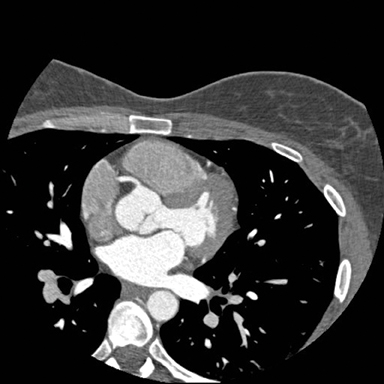

This image from an iCT scanner was done to evaluate coronary artery disease. The scan parameters were: 100 kVp, 50 mAs, CTDI vol 6.3 mGy, DLP 68.3 mGy x cm, iDose4 level = 3, effective dose 0.9 mSv. More images are below.

Logan described how image noise is an important determinant of image quality. It is inversely related to the X-ray beam energy. “Although a reduction in tube current and tube current voltage causes a resultant decrease in radiation dose,” he said, “this also increases image noise, which may compromise image quality.”

Because iDose4 significantly improves spatial resolution and preserves the “natural” appearance of images, image quality improvements are achieved.

By having two iCT scanners, SOMC can provide a continuum of care for advanced cardiovascular studies. In addition, emergency patients, inpatients and outpatients benefit from the range of clinical applications enabled by the sophisticated capabilities of the iCT.